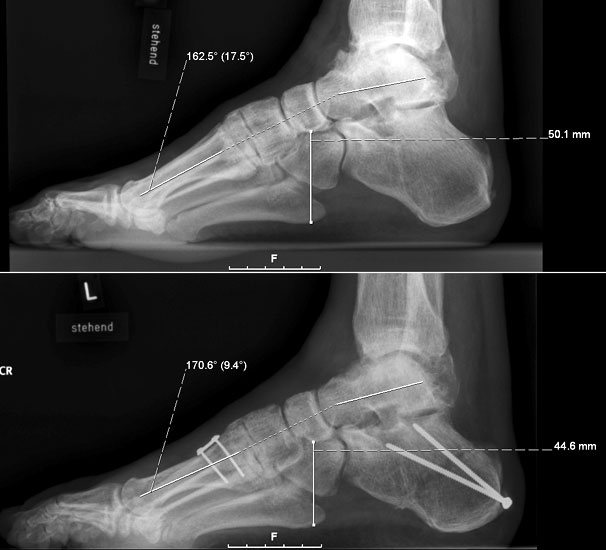

Dorsalflektierende Osteotomien des medialen Mittelfuβes (Abb. 6 – 9, Video 4)

• Erhöhter lateraler Talo-Metatarsale I Winkel (Meary-Winkel) als Ausdruck des plantarflektierten medialen Mittelfuβes, insbesondere im "forefoot driven hindfoot varus" (positiver Coleman block Test).

Die reduzierte Steilstellung des 1. Strahls wirkt sich positiv auf den Rückfuβ varus und den Vorfuβ adductus aus. Auch die relative Dorsalflexion des Talus in der Sprunggabel mit anterioren OSG-Impingement und verringerter OSG-Dorsalflexion wird verbessert.

Generell wird die dorsalflektierende MT I Osteotomie (Abb. 6 und 7) nicht isoliert ausgeführt, sondern ist Teil der gesamten Hohlfuβ-Korrektur. Beim absolut flexiblen Hohlfuβ ist sie gelegentlich zusammen mit einem Peroneus longus auf brevis oder einem Release der Plantarfaszie ausreichend. Diese Osteotomie ist einfach durchzuführen und hat eine geringe Pseudarthroserate.

Eine ähnliche dorsalflektierende Osteotomie des Os cuneiforme mediale (reversed Cotton Osteotomie, Abb. 8 und 9), ebenfalls mit Entnahme eines dorsal basierten Knochenkeils, ist effektiver im Ausmass der Korrektur, jedoch oftmals wegen der Insertion des kräftigen Lisfranc-Ligaments nur schwierig zu schliessen.

• Evaluation der gewünschten Korrektur mit simulierter, plantigrader Belastung des Vorfuβes: MT I und V Köpfchen sollten auf gleicher Höhe in Relation zur Tibiaachse sein, bei prominenten MT II und III Köpfchen entsprechende dorsalflektierende Osteotomien (Basis des Keils 2 bis 4 mm).